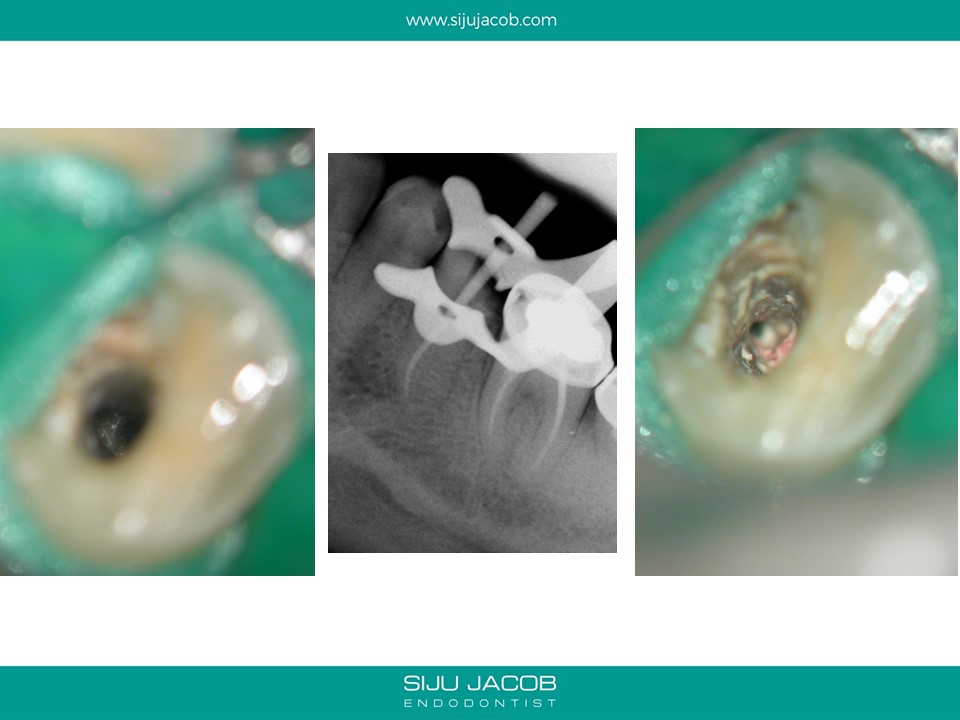

Previous clinician started this case and referred it when the patient continued to have pain. This was a two-rooted mandibular pre-molar with the canals present at a very odd angle and position. It was difficult to clean, shape and pack because the canals were very close to each other. When obturating these canals, I usually down pack one canal, then use a small micro-opener to remove the G.p that usually blocks the second canal and then down pack the second canal.